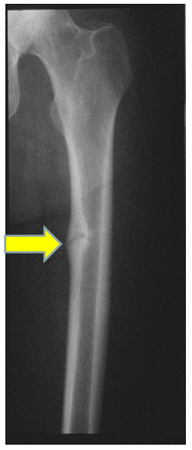

Widening of the epiphyseal plate, and loss of definition of the zone of provisional calcification at the epiphyseal/metaphyseal interface, are early signs of rickets. Looser's pseudofractures, which lie perpendicular to the cortical margins with the characteristic sclerotic borders, are a pathognomonic finding in osteomalacia. Classic metaphyseal lesions also known as bucket-handle fractures can be observed at the growth plates of long bones.[95]Charoenngam N, Ayoub D, Holick MF. Nutritional rickets and vitamin D deficiency: consequences and strategies for treatment and prevention. Expert Rev Endocrinol Metab. 2022 Jul;17(4):351-64.

[Figure caption and citation for the preceding image starts]: Radiograph of the femoral shaft in a patient with osteomalacia demonstrating a 'pseudofracture' (also known as Looser's zone) on the medial aspect of the mid-femoral shaftFrom the collection of Bridget Sinnott, MD [Citation ends].